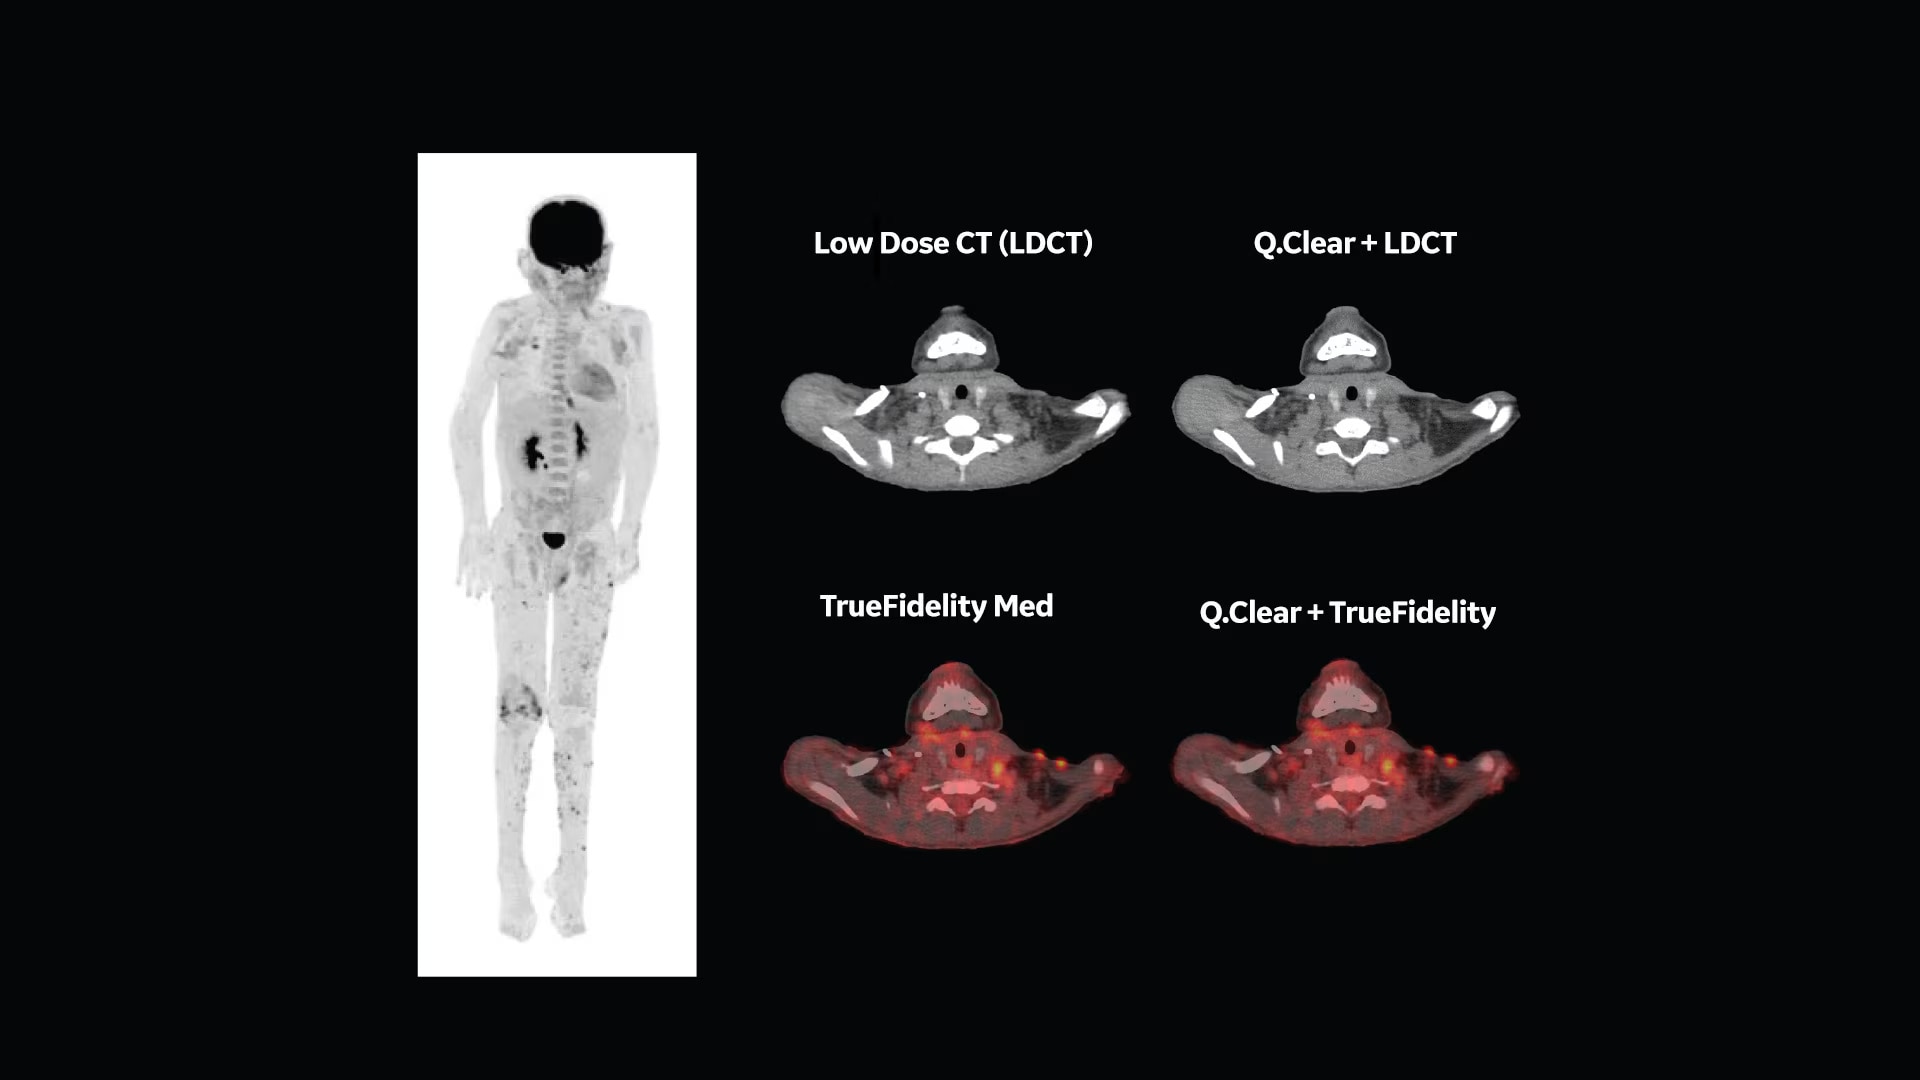

See what you need to see with TrueFidelity

For years, low dose was the benchmark for image quality by which every CT image was held. We helped set the standard for low-dose imaging back in 2008 by introducing the industry’s first iterative reconstruction technology capable of lowering dose. Over the years, the benchmark has changed. While dose is still important, radiologists are looking for an image texture reminiscent of the text-book quality images they studied in medical school.

Take your CT experience even further on a system designed for TrueFidelity, our latest innovation in CT image reconstruction technology that uses a deep-learning based reconstruction engine to combine the low-dose CT you expect with the image texture you want.